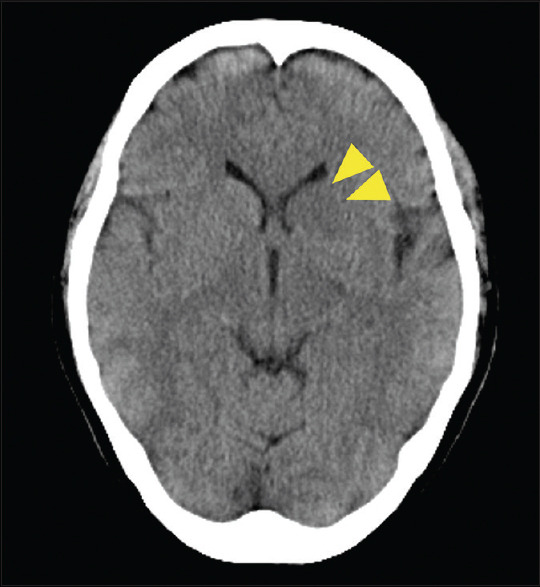

勒米尔综合征是一种罕见的疾病,以颈内静脉血栓性静脉炎和远处器官转移为特征。该病发生在喉部或牙齿部位的厌氧菌感染之后;中枢神经系统受累的情况并不多见。一名 50 岁的妇女出现意识障碍。发病前,她因牙痛接受了数天的牙科治疗。对比增强计算机断层扫描(CT)显示头颈部有脓肿,颈内静脉有大量血栓,诊断为莱米埃尔综合征。经过手术引流和抗菌治疗后,症状有所好转,患者于第 58 天出院。在这个病例中,由于大量脑静脉血栓导致静脉充血,并发了静脉中风,从而并发了莱米埃尔综合征。莱米埃尔综合征患者可能因血栓导致静脉中风,磁共振成像或 CT 静脉相成像可帮助诊断。

Lemierre's syndrome is a rare disease characterized by thrombophlebitis of the internal jugular vein and metastasis to distant organs. It occurs after an anaerobic infection of the larynx or dental region; the central nervous system involvement is infrequent. A 50-year-old woman presented with impaired consciousness. She had undergone several days of dental treatment for a toothache before presentation. Contrast-enhanced computed tomography (CT) revealed a head-and-neck abscess and a massive thrombus in the internal jugular vein, and a diagnosis of Lemierre's syndrome was made. After symptoms improved with surgical drainage and antimicrobial therapy, the patient was discharged on day 58. In this case, Lemierre's syndrome was complicated by a venous stroke caused by venous congestion due to a massive cerebral venous thrombus. Venous stroke due to thrombi may occur in patients with Lemierre's syndrome, and magnetic resonance imaging or CT with venous phase imaging may aid in the diagnosis.